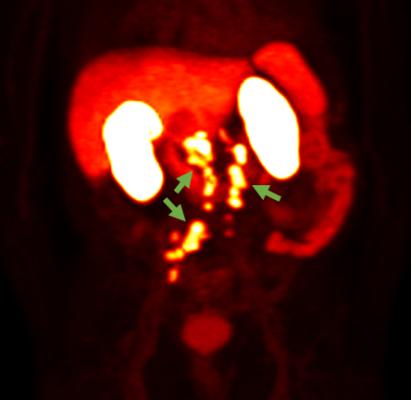

18F-rhPSMA-7.3 PET Photo courtesy of Blue Earth Diagnostics. General use: This 18F-rhPSMA-7.3 PET image shows prostate cancer spread beyond the prostate region. Technical use: This 18F-rhPSMA-7.3 PET image shows detection of recurrent prostate cancer in several retroperitoneal lymph nodes, as indicated by the green arrows.